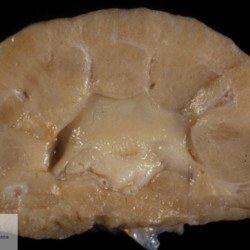

Etiquetes: B-590/92 3 total Canine Specie: Canine Organ: Kidney Lesion: Dysplasia Lesion modifier: - Disease: Juvenile nephropathy Files/Expedient: B-590/92 Not viewed Canine Specie: Canine Organ: Kidney Lesion: Dysplasia Lesion modifier: - Disease: Juvenile nephropathy Files/Expedient: B-590/92 Not viewed Canine Specie: Canine Organ: Kidney Lesion: Dysplasia Lesion modifier: - Disease: Juvenile nephropathy Files/Expedient: B-590/92 Not viewed Títol Select...Avian (Exotic) (110)Avian (Poultry) (76)Bovine (317)Canine (935)Caprine (47)Equine (257)Feline (326)Ferret (19)General (127)Marine mammal (22)Non-human primate (20)Ovine (328)Porcine (379)Rabbit (61)Reptile (38)Rodent (28)Wildlife (91) Format Select...- (60)Abomasum (37)Adrenal gland (10)Blood (7)Blood vessel (50)Body as a whole (19)Bone (57)Bone marrow (21)Brain (93)Cloaca (1)Diaphragm (2)Ear (5)Esophagus (39)Eye (16)Fetus (12)Gallbladder (23)Gizzard (2)Heart (265)Intestine (356)Joint (32)Kidney (443)Larynx (5)Liver (326)Lung (264)Lymph node (91)Mammary gland (10)Mediastinum (1)Muscle (22)Nasal cavity (22)Nerve (7)Omasum (5)Oral cavity (63)Ovary (14)Oviduct (8)Pancreas (7)Parathyroid (5)Penis (10)Peritoneum (65)Pharynx (9)Pituitary gland (6)Placenta (7)Prostate (8)Proventriculus (3)Reticulum (1)Rumen (28)Sinus (7)Skin (181)Spinal cord (15)Spleen (105)Stomach (125)Teeth (1)Testicle (11)Thoracic cavity (31)Thymus (13)Thyroid gland (5)Tongue (32)Tonsils (11)Trachea (11)Urethra (5)Urinay bladder (61)Uterus (27)Vagina (1)Vulva (1)Yolk sac (1) Cobertura Select...- (152)Abomasitis (26)Abscess (27)Acidosis (1)Adenocarcinoma (20)Adenoma (9)Aerosacculitis (6)Agenesis (1)Agnathia (1)Alopecia (7)Amyloidosis (12)Aneurysm (6)Angiectasis (1)Anthracosis (1)Arteritis (11)Arthritis (15)Arthrogryposis (6)Artifact (4)Ascites (13)Atelectasis (8)Atherosclerosis (5)Atresia (1)Atrial septal defect (2)Atrophy (10)Autolysis (7)Bronchitis (6)Bronchopneumonia (26)Cachexia (2)Carcinoma (103)Cardiomyopathy (19)Cellulitis (2)Chemodectoma (4)Cholangiohepatitis (4)Cholangitis (19)Cholecystitis (4)Cholestasis (5)Chondrodysplasia (2)Chondrosarcoma (2)Chronic passive congestion (13)Chylothorax (2)Cirrhosis (6)Coelomitis (3)Coenurus cerebralis (4)Colitis (40)Congestion (17)Conjunctivitis (5)Coronitis (3)Cryptorchidism (3)Cyst (25)Cystitis (24)Dermatitis (69)Diaphragmatic hernia (4)Dilation (28)Discospondylitis (1)Disseminated intravascular coagulation (7)Dyschondroplasia (1)Dysplasia (29)Ectopia cordis (1)Ectopic ureter (1)Edema (55)Emphysema (5)Encephalitis (5)Endocardiosis (14)Endocarditis (26)Endometritis (5)Enteritis (118)Enterolith (6)Epulis (3)Esophagitis (14)Fasciitis (1)Fibrosis (7)Fibrous osteodystrophy (8)Fistula (1)Folliculitis (3)Fracture (2)Gastritis (34)Gingivitis (5)Glioma (8)Glomerulonephritis (21)Glossitis (25)Glycogenosis (1)Gout (8)Granuloma (2)Granulosa cell tumor (4)Hemangioma (9)Hemangiosarcoma (46)Hematoma (8)Hemoglobinuria (2)Hemopericardium (12)Hemoperitoneum (2)Hemorrhage (100)Hemosiderosis (7)Hemothorax (2)Hepatitis (78)Hernia (11)Histiocytosis (3)Hydatid cyst (11)Hydrocephalus (9)Hydrometra (1)Hydronephrosis (22)Hydropericardium (6)Hydrothorax (3)Hydroureter (5)Hyperkeratosis (8)Hyperostosis (4)Hyperplasia (37)Hypertrophy (9)Hypopigmentation (1)Hypoplasia (7)Hypopyon (1)Impaction (6)Infarction (63)Insulinoma (6)Intussusception (5)Jaundice (17)Laminitis (2)Laryngitis (2)Leiomyoma (5)Leukemia (13)Lipidosis (36)Lipoma (7)Lymphadenitis (45)Lymphadenopathy (7)Lymphangiectasia (6)Lymphangitis (5)Lymphoma (221)Malacia (11)Malignant melanoma (15)Mast cell tumor (11)Mastitis (8)Megaesophagus (2)Melanosis (3)Melena (4)Meningioma (6)Meningitis (6)Meningocele (2)Meningoencephalitis (5)Mesothelioma (5)Methemoglobinemia (2)Mineralization (10)Mucocele (5)Mucometra (1)Multilobular bone tumor (1)Mummification (3)Myelofibrosis (1)Myocarditis (4)Myositis (5)Necrosis (81)Nephritis (113)Nephroblastoma (6)Nephrosclerosis (1)Nephrosis (14)Neuritis (1)Obstruction (13)Omasitis (4)Omphalitis (1)Omphalophlebitis (7)Orchitis (4)Osteoarthrosis (5)Osteomyelitis (9)Otitis (2)Palatoschisis (3)Pancreatitis (3)Panniculitis (3)Papilloma (7)Parakeratosis (14)Patent ductus arteriosus (6)Peliosis hepatis (1)Perforation (17)Pericarditis (35)Peritonitis (39)Persistent right aortic arch (1)Pharyngitis (2)Pheochromocytoma (2)Phlebitis (2)Placentitis (6)Pleuritis (21)Pleuropneumonia (24)Pneumonia (109)Pneumothorax (3)Polycystosis (14)Polyp (5)Polyserositis (6)Posthitis (1)Proctitis (4)Prolapse (3)Prostatitis (3)Proventriculitis (1)Pyelonephritis (24)Pyometra (6)Pyothorax (4)Rhinitis (11)Rumenitis (6)Rupture (24)Salpingitis (3)Sarcoma (57)Sclerosis (1)Scoliosis (2)Seminoma (2)Sequestrum (2)Serous atrophy (14)Sinusitis (7)Splenitis (14)Splenomegaly (9)Spondylitis (6)Spondylosis (1)Stenosis (9)Stomatitis (32)Tenosynovitis (2)Teratoma (3)Thricobezoar (2)Thrombosis (16)Tonsilitis (4)Torsion (13)Tracheitis (4)Tympany (7)Typhlitis (8)Typhlocolitis (4)Ulcer (43)Urethritis (1)Urolithiasis (36)Uroperitoneum (1)Uveitis (1)Vasculitis (15)Ventricular septal defect (3)Volvulus (11) Matèria Select... - (14)- (1653)- (152)Abomasitis - Catarrhal (2)Abomasitis - Catarrhal-hemorrhagic (1)Abomasitis - Chronic (1)Abomasitis - Fibrinous-necrotizing (2)Abomasitis - Hyperplasic (5)Abomasitis - Hyperplasic - Chronic (1)Abomasitis - Necrotic (1)Abomasitis - Necrotizing (2)Abomasitis - Ulcerative (5)Adenocarcinoma (9)Aerosacculitis - Granulomatous (1)Amyloidosis - Chronic (1)Arteritis - Necrotic (2)Arteritis - Necrotizing (1)Arthritis - Chronic (4)Arthritis - Fibrinous-purulent (3)Arthritis - Serous (4)Arthritis - Subacute (1)Ascites - Serous (1)Atrophy - Serous (1)Bronchitis - Catarrhal (3)Bronchitis - Suppurative (1)Bronchopneumonia - Catarrhal-purulent (17)Bronchopneumonia - Fibrinous (1)Bronchopneumonia - Granulomatous (1)Bronchopneumonia - Purulent (1)Bronchopneumonia - Suppurative (5)Carcinoma - Adenocarcinoma (33)Carcinoma - Adenocarcinoma - Hepatocellular (2)Carcinoma - Adenocarcinoma - Mucinous (1)Carcinoma - Basosquamous (1)Carcinoma - Cholangiocellular (3)Carcinoma - Hepatocellular (4)Carcinoma - Metastatic (3)Carcinoma - Squamous cell carcinoma (13)Carcinoma - Transitional cell (2)Cardiomyopathy - Dilated (13)Cardiomyopathy - Hypertrophic (6)Cellulitis - Necrotizing (1)Cholangitis - Chronic (8)Cholangitis - Hyperplasic (3)Cholecystitis - Fibrinous-necrotizing (1)Coelomitis - Fibrinous (1)Coelomitis - Granulomatous (1)Colitis - Catarrhal (3)Colitis - Catarrhal-hemorrhagic (1)Colitis - Fibrinous (1)Colitis - Fibrinous-necrotizing (1)Colitis - Fibrinous-necrotizing (Diphtheritic) (6)Colitis - Granulomatous (2)Colitis - Hemorrhagic (4)Colitis - Hemorrhagic-necrotizing (3)Colitis - Necrotizing (2)Colitis - Ulcerative (6)Congestion - Chronic (2)Conjunctivitis - Hyperplasic (1)Conjunctivitis - Purulent (3)Coronitis - Ulcerative (1)Cystitis - Chronic (3)Cystitis - Fibrinous (1)Cystitis - Fibrinous-necrotizing (1)Cystitis - Follicular (1)Cystitis - Hemorrhagic (6)Cystitis - Hemorrhagic-ulcerative (1)Cystitis - Necrotizing (9)Cystitis - Perforated (1)Dermatitis - Granulomatous (14)Dermatitis - Hyperkeratotic (10)Dermatitis - Hyperplasic (proliferative) (1)Dermatitis - Hyperplastic (10)Dermatitis - Necrotizing (4)Dermatitis - Pustular (4)Dermatitis - Ulcerative (2)Dilation - Chronic (1)Discospondylitis - Necrotizing (1)Dysplasia - Follicular (5)Edema - Interstitial (6)Emphysema - Interstitial (1)Encephalitis - Granulomatous (1)Encephalitis - Nonsuppurative (1)Endocardiosis - Mitral (7)Endocardiosis - Mitral - Chronic (5)Endocarditis - Valvular (6)Endocarditis - Valvular - Mitral (7)Endocarditis - Valvular - Pulmonic (1)Endocarditis - Valvular - Subacute (1)Endocarditis - Valvular - Subaortic (5)Endocarditis - Valvular - Tricuspid (4)Endometritis - Purulent (3)Endometritis - Purulent-hemorrhagic (2)Enteritis - Catarrhal (23)Enteritis - Catarrhal - Acute (1)Enteritis - Catarrhal-hemorrhagic (5)Enteritis - Catarrhal-hemorrhagic - Acute (2)Enteritis - Fibrinous (16)Enteritis - Fibrinous - Acute (3)Enteritis - Fibrinous-necrotizing (7)Enteritis - Granulomatous (14)Enteritis - Granulomatous - Chronic (1)Enteritis - Granulomatous - Multifocal (1)Enteritis - Hemorrhagic (17)Enteritis - Hemorrhagic - Acute (1)Enteritis - Hemorrhagic-necrotizing (1)Enteritis - Hyperplasic (proliferative) (4)Enteritis - Necrotizing (4)Enteritis - Necrotizing - Acute (1)Enteritis - Necrotizing - Hemorrhagic (1)Enteritis - Necrotizing-ulcerative (2)Enteritis - Ulcerative (1)Enteritis - Ulcerative-hemorrhagic (1)Esophagitis - Erosive-ulcerative (6)Esophagitis - Necrotizing (4)Esophagitis - Ulcerative (1)Esophagitis - Ulcerative-necrotizing (1)Fasciitis - Fibrinous-purulent (1)Folliculitis - Purulent (2)Gastritis - Catarrhal (2)Gastritis - Chronic (1)Gastritis - Follicular (1)Gastritis - Hemorrhagic (2)Gastritis - Hemorrhagic-necrotizing (1)Gastritis - Hypertrophic (2)Gastritis - Inclusion bodies (1)Gastritis - Mineralization (1)Gastritis - Mycotic (1)Gastritis - Necrotizing (2)Gastritis - Ulcerative (6)Gastritis - Uremic (3)Gingivitis - Erosive (2)Gingivitis - Hyperplasic (proliferative) (1)Gingivitis - Necrotizing (1)Glomerulonephritis - Chronic (7)Glomerulonephritis - Membranoproliferative (3)Glomerulonephritis - Membranoproliferative - Chronic (1)Glomerulonephritis - Membranous (3)Glomerulonephritis - Membranous - Chronic (1)Glomerulonephritis - Proliferative (2)Glomerulonephritis - Subacute (1)Glossitis - Erosive (2)Glossitis - Granulomatous (6)Glossitis - Hyperplasic (1)Glossitis - Hyperplasic (proliferative) (2)Glossitis - Hyperplastic (1)Glossitis - Necrotizing (2)Glossitis - Necrotizing - Focal (1)Glossitis - Ulcerative (6)Glossitis - Ulcerative - Multifocal (1)Glossitis - Ulcerative - Subacute (1)Glycogenosis (1)Granuloma - Eosinophilic (1)Hemangiosarcoma - Metastatic (2)Hemorrhage - Acute (1)Hemorrhage - Subcapsular (3)Hepatitis - Abscess (9)Hepatitis - Acute (3)Hepatitis - Chronic (4)Hepatitis - Chronic interstitial (6)Hepatitis - Granulomatous (7)Hepatitis - Interstitial - Multifocal (1)Hepatitis - Interstitial - Subacute (1)Hepatitis - Necrotizing (17)Hepatitis - Necrotizing - Acute (2)Hepatitis - Necrotizing - Hemorrhagic (1)Hepatitis - Necrotizing - Subacute (1)Hepatitis - Pyogranulomatous (7)Hepatitis - Subacute (4)Hydronephrosis - Chronic (1)Hydropericardium - Chronic (1)Hyperplasia - Erythroid (1)Hyperplasia - Lymphoid (3)Hyperplasia - Myeloid (1)Hyperplasia - Nodular (8)Hypertrophy - Concentric (2)Hypertrophy - Eccentric (3)Infarction - Acute (17)Infarction - Acute - Multifocal (2)Infarction - Chronic (5)Infarction - Chronic - Multifocal (1)Infarction - Subacute (18)Infarction - Subacute - Focal (2)Laminitis - Chronic (2)Laryngitis - Necrotic (1)Laryngitis - Necrotizing (1)Leukemia - Lymphoid leukemia (2)Leukemia - Non-lymphoid leukemia (6)Lipidosis - Multifocal (1)Lipidosis - Panlobular (1)Lipidosis - Panlobular - Generalized (2)Lymphadenitis - Granulomatous (24)Lymphadenitis - Granulomatous - Chronic (3)Lymphadenitis - Hemorrhagic (1)Lymphadenitis - Necrotizing (5)Lymphadenitis - Necrotizing (caseous) (11)Lymphangitis - Granulomatous (1)Lymphangitis - Purulent (1)Lymphangitis - Ulcerative (1)Lymphoma - Alimentary lymphoma (7)Lymphoma - Cutaneous lymphoma (6)Lymphoma - Lymphosarcoma (2)Lymphoma - Mediastinal lymphoma (1)Lymphoma - Multicentric lymphoma (29)Malignant melanoma - Malignant (1)Malignant melanoma - Metastatic (1)Mast cell tumor - Metastatic (1)Mastitis - Fibrinous-purulent (2)Mastitis - Necrotic (1)Mastitis - Purulent (3)Mastitis - Suppurative (1)Meningitis - Fibrinous-purulent (2)Meningitis - Purulent (4)Meningoencephalitis - Necrotizing (3)Meningoencephalitis - Nonsuppurative (2)Mineralization - Metastatic (4)Myocarditis - Fibrous - Chronic (1)Myocarditis - Granulomatous (1)Myositis - Purulent (2)Necrosis - Acute (1)Necrosis - Cortical (5)Necrosis - Follicular (1)Necrosis - Papillary (8)Necrosis - Papillary - Acute (3)Necrosis - Subacute (3)Necrosis - Tubular (6)Nephritis - Embolic (2)Nephritis - Embolic suppurative (7)Nephritis - Granulomatous (27)Nephritis - Granulomatous - Chronic (1)Nephritis - Granulomatous - Multifocal (1)Nephritis - Interstitial (6)Nephritis - Interstitial - Acute (4)Nephritis - Interstitial - Chronic (41)Nephritis - Interstitial - Subacute (12)Nephritis - Purulent (7)Nephritis - Purulent - Acute (2)Nephritis - Purulent - Multifocal (3)Nephrosis - Cholemic (3)Nephrosis - Hemoglobinuric (10)Omasitis - Fibrinous-necrotizing (1)Omasitis - Hyperkeratotic (1)Omasitis - Necrotizing (2)Omphalophlebitis - Fibrinous-purulent (2)Omphalophlebitis - Purulent (3)Orchitis - Necrotizing (1)Osteomyelitis - Necrotizing (7)Osteomyelitis - Purulent (2)Otitis - Necrotizing (1)Otitis - Proliferative (1)Pancreatitis - Acute (1)Pancreatitis - Chronic (1)Pancreatitis - Granulomatous (1)Panniculitis - Fibrinous-purulent (1)Panniculitis - Necrotic (1)Panniculitis - Parasitic (1)Perforation - Acute (2)Pericarditis - Fibrinous (19)Pericarditis - Fibrinous - Subacute (1)Pericarditis - Fibrinous-necrotizing (1)Pericarditis - Fibrinous-purulent (3)Pericarditis - Fibrous (1)Pericarditis - Fibrous - Chronic (1)Pericarditis - Gangrenous (6)Pericarditis - Granulomatous (1)Pericarditis - Granulomatous - Chronic (2)Peritonitis - Acute (1)Peritonitis - Fibrinous (11)Peritonitis - Fibrinous - Subacute (1)Peritonitis - Fibrinous-purulent (5)Peritonitis - Fibrous (3)Peritonitis - Granulomatous (6)Peritonitis - Purulent (1)Peritonitis - Purulent-hemorrhagic (1)Peritonitis - Pyogranulomatous (3)Pharyngitis - Fibrinous-necrotizing (1)Pharyngitis - Ulcerative (1)Pheochromocytoma - Metastatic (1)Phlebitis - Purulent (1)Placentitis - Fibrinous-necrotizing (1)Placentitis - Necrotic (1)Placentitis - Necrotizing (1)Pleuritis - Chronic (1)Pleuritis - Fibrinous (3)Pleuritis - Fibrinous-purulent (2)Pleuritis - Fibrous (2)Pleuritis - Granulomatous (3)Pleuritis - Hyperplastic (2)Pleuritis - Purulent (2)Pleuritis - Pyogranulomatous (1)Pleuropneumonia - Fibrinous (13)Pleuropneumonia - Fibrinous-necrotizing (5)Pleuropneumonia - Granulomatous (2)Pleuropneumonia - Hemorrhagic-necrotizing (4)Pneumonia - Aspiration (11)Pneumonia - Bronchointerstitial (4)Pneumonia - Bronchointerstitial - Subacute (1)Pneumonia - Embolic (5)Pneumonia - Granulomatous (37)Pneumonia - Granulomatous - Multifocal (4)Pneumonia - Hemorrhagic-necrotizing (2)Pneumonia - Interstitial (7)Pneumonia - Interstitial - Acute (8)Pneumonia - Interstitial - Chronic (6)Pneumonia - Interstitial - Subacute (15)Pneumonia - Necrotizing (2)Pneumonia - Pyogranulomatous (2)Pneumonia - Verminous (5)Polyserositis - Fibrinous (6)Polyserositis - Fibrous (1)Proctitis - Fibrinous-necrotizing (1)Proctitis - Parasitic (2)Prostatitis - Purulent (1)Pyelonephritis - Acute (2)Pyelonephritis - Chronic (3)Rhinitis - Catarrhal (2)Rhinitis - Fibrinous (1)Rhinitis - Granulomatous (4)Rhinitis - Purulent (3)Rumenitis - Acute (1)Rumenitis - Erosive (1)Rumenitis - Necrotizing (1)Rupture - Acute (3)Sarcoma - Fibrosarcoma (12)Sarcoma - Hemangiosarcoma (11)Sarcoma - Histiocytic (7)Sarcoma - Metastatic (1)Sarcoma - Multilobular tumor of bone (1)Sequestrum - Chronic (2)Sinusitis - Suppurative (1)Splenitis - Granulomatous (8)Splenitis - Granulomatous - Chronic (1)Splenitis - Necrotizing (3)Splenitis - Necrotizing (caseous) (2)Spondylitis - Necrotizing (2)Stenosis - Intestinal (1)Stenosis - Valvular - Subaortic (4)Stomatitis - Erosive (12)Stomatitis - Erosive-ulcerative (3)Stomatitis - Fibrinous-necrotizing (1)Stomatitis - Fibrinous-necrotizing (Diphtheritic) (1)Stomatitis - Granulomatous (1)Stomatitis - Hyperplasic (1)Stomatitis - Hyperplasic (proliferative) (1)Stomatitis - Necrotizing (2)Stomatitis - Ulcerative (5)Stomatitis - Ulcerative - Multifocal (1)Stomatitis - Ulcerative-necrotizing (1)Tonsilitis - Necrotizing (4)Torsion - Acute passive hyperemia (5)Tracheitis - Catarrhal (3)Tracheitis - Fibrinous (1)Tracheitis - Granulomatous (1)Typhlitis - Catarrhal (1)Typhlitis - Fibrinous-necrotizing (2)Typhlitis - Hemorrhagic (2)Typhlitis - Ulcerative-hemorrhagic (1)Typhlocolitis - Fibrinous-necrotizing (2)Typhlocolitis - Proliferative (1)Ulcer - Chronic (6)Ulcer - Multifocal (2)Ulcer - Mycotic (1)Ulcer - Perforated (6)Urethritis - Hemorrhagic (1)Urolithiasis - Chronic (2)Uveitis - Granulomatous (1)Vasculitis - Granulomatous (1)Vasculitis - Necrotizing (1) Editor Select...- (1970)Acidosis (2)Actinobacillosis (Pleuropneumonia) (11)Aelurostrongylosis (2)African horse sickness (13)African swine fever (14)Alopecia X (1)Anaplasmosis (4)Anthrax (2)Aortic thromboembolism (feline) (7)Ascariasis (15)Aspergillosis (18)Atopic dermatitis (1)Atrophic rhinitis (3)Babesiosis (6)Blackhead (1)Bluetongue (11)Border disease (2)Bovine viral diarrhea (21)Brucellosis (2)Candidiasis (5)Canine distemper (14)Caprine arthritis-encephalitis (2)Capture myopathy (1)Cardiac insufficiency (17)Caseous lymphadenitis (7)Chlamydiosis (2)Classical swine fever (19)Clostridiosis (19)Coccidiosis (9)Coenurosis (4)Colibacillosis (21)Contagious ecthyma (7)Copper toxicosis (11)Cowdriosis (Heartwater) (3)Cryptococcosis (3)Cryptosporidiosis (2)Cysticercosis (23)Demodicosis (1)Diabetes (1)Dicrocoeliosis (5)Dictyocaulosis (4)Dirofilariasis (7)Discoid lupus erythematosus (3)Echinococcosis (17)Edema disease (7)Egg drop syndrome (1)Encephalitozoonosis (5)Enterotoxemia (1)Enzootic bovine leukosis (46)Epitheliogenesis imperfecta (3)Equine rhinopneumonitis (2)Equine verminous arteritis (strongylosis) (7)Erysipelas (5)Exudative epidermitis (7)Fasciolasis (11)Feline eosinophilic dermatoses (1)Feline hepatic lipidosis (8)Feline histiocytosis (4)Feline infectious peritonitis (38)Feline leukemia (4)Feline lower urinary tract disease (3)Feline panleukopenia (16)Feline viral rhinotracheitis (1)Flea allergy dermatitis (1)Foot and mouth disease (2)Gasterophilosis (4)Glasser's disease (15)Gousiekte (4)Gout (6)Haemonchosis (9)Hemolytic anemia (4)Hemorrhagic diathesis (1)Hepatic insufficiency (11)Hepatosis dietetica (7)Herpesvirosis (6)Hyperadrenocorticism (7)Hyperparathyroidism (10)Hypertrophic osteopathy (6)Hypervitaminosis D (1)Hypodermosis (1)Inclusion body hepatitis (4)Infectious bovine rhinotracheitis (5)Infectious bronchitis (5)Infectious canine hepatitis (13)Influenza (4)Juvenile nephropathy (8)Lamb dysentery (4)Leishmaniasis (28)Leptospirosis (1)Leukosis (5)Listeriosis (4)Lumpy skin disease (3)Maedi-visna (4)Malignant catarrhal fever (12)Mange (6)Mannheimiosis (5)Marek's disease (7)Metabolic bone disease (2)Mucoid enteropathy (5)Mulberry heart disease (5)Myasis (1)Mycobacteriosis (22)Mycosis fungoides (6)Myxomatosis (3)Necrobacillosis (5)Neonatal isoerythrolysis (6)Nocardiosis (4)Oestrosis (2)Onchocerciasis (1)Osteochondrosis (1)Ostertagiosis (6)Ovine pulmonary adenocarcinoma (5)Oxyuriasis (1)Pacheco's disease (4)Papillomatosis (6)Paratuberculosis (18)Parvovirosis (17)Pasteurellosis (11)Pemphigus foliaceus (1)Periodontal disease (1)Polioencephalomalacia of ruminants (4)Polyarteritis nodosa (3)Polycystic kidney disease (13)Porcine circovirosis (11)Porcine dermatitis and nephropathy syndrome (9)Porcine proliferative enteropathy (4)Porcine reproductive and respiratory syndrome (6)Porcine stress syndrome (1)Pox (13)Pregnancy toxemia (3)Proventricular dilatation disease (2)Pseudotuberculosis (yersiniosis) (2)Psittacine beak and feather disease (PBFD) (5)Pyoderma (4)Q fever (4)Rabbit hemorrhagic disease (2)Renal insufficiency (12)Reticuloendotheliosis (2)Rhodococcosis (1)Rickets (1)Rinderpest (2)Salmonellosis (34)Sarcosporidiosis (2)Schmallenberg (7)Septicemia (23)Spirocercosis (11)Streptococcosis (5)Strongylosis (1)Swine dysentery (5)Systemic coronavirosis (5)Tetralogy of Fallot (5)Theileriosis (13)Thromboembolism (5)Toxoplasmosis (11)Transmissible viral proventriculitis (1)Traumatic reticuloperitonitis (3)Traumatism (16)Tuberculosis (58)Ulcerative lymphangitis (1)Uremic syndrome (20)Viral arthritis (6)White muscle disease (9)Wobbler syndrome (2)Xanthomatosis (1)Zygomycosis (4) Idioma Select...- (1180)Bacterial (501)Degeneration (106)Fungal (46)Hemodynamic (112)Idiopathic (22)Inflammation (58)Malformation (88)Neoplasia (343)Nutritional (41)Parasitic (243)Physical/Chemical (93)Toxic (44)Viral (304) Ítem destacat Canine Acanthomatous ameloblastoma (acanthomatous epuli). Note tooth deviation consequence of invasion of local alveolar bone. Courtesy of Dr. Silvia Moreno